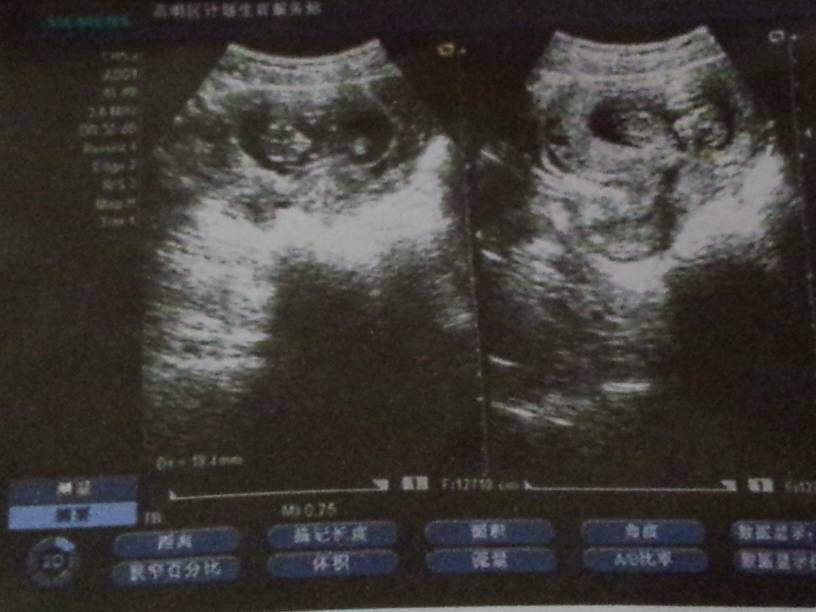

孕十一周彩色多普勒超声图,帮忙看下胎儿是否正常? 孕十一周彩色多普勒超声图,帮忙看下胎儿是否正常? 点击展开 一个人,也狠好 2014-05-17 14:45 为您推荐: 其他回答 从图像上模糊的看,胎儿已成形,符合怀孕月份,至于是否有畸形要到19周以后看比较清楚。 张笑珠 2014-05-17 15:02 相关问题 胎儿心脏彩色多普勒超声心动图在华西妇女儿童医院挂哪科 孕十六周去做b超,超声测试,宫内单胎,胎心可见胎儿双顶径28,头围109腹径25,股骨长度16 孕22周时超声检查出胎儿发现左侧侧脑宽约